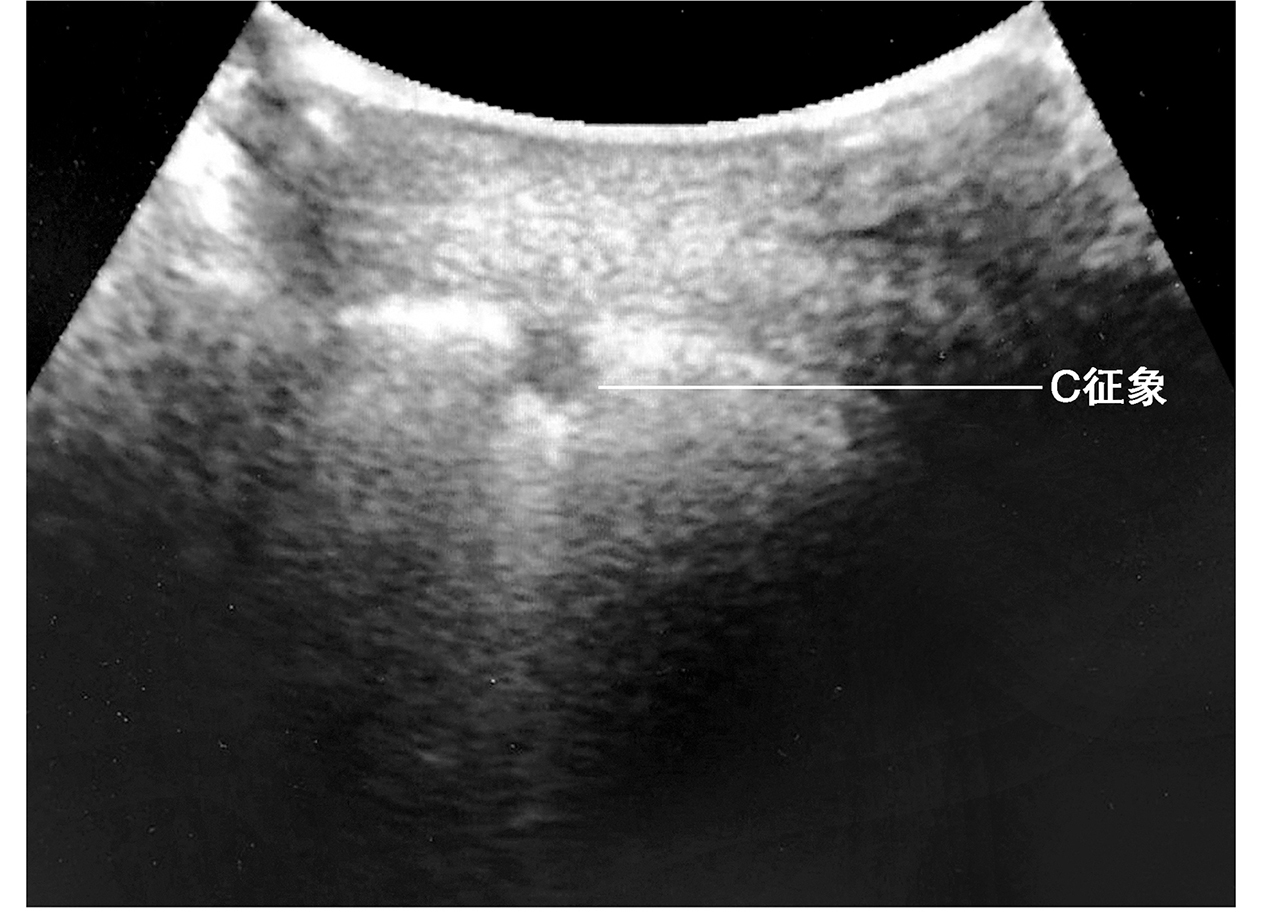

(3)C征象

提示前胸壁的局灶性肺实变(图5)。血行播散的重症肺炎往往可以见到弥漫分布的C线。

图5 C征象

肺炎患者,前胸壁出现的局灶性肺泡塌陷,肺表面的高回声亮线呈弧形凹陷,即C征象